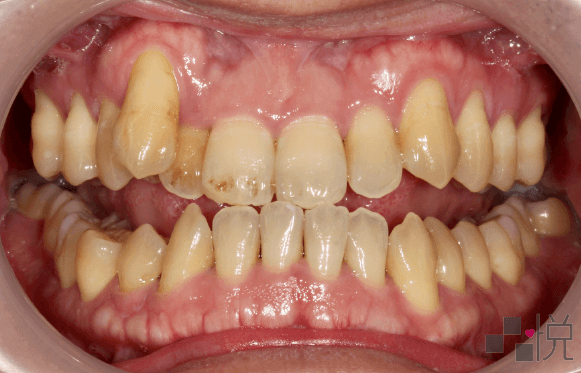

本案例治療前有輕微的「骨性戽斗」,齒列擁擠,上顎及下顎中線偏差,合併有前牙和後牙錯咬,而後牙錯咬造成了咬合干擾,使得下顎往右側歪斜。

採用不拔牙的矯正治療,並且讓下顎順時針旋轉改善戽斗的外觀。牙齒矯正後咬合干擾消失,同時改善臉部歪斜。